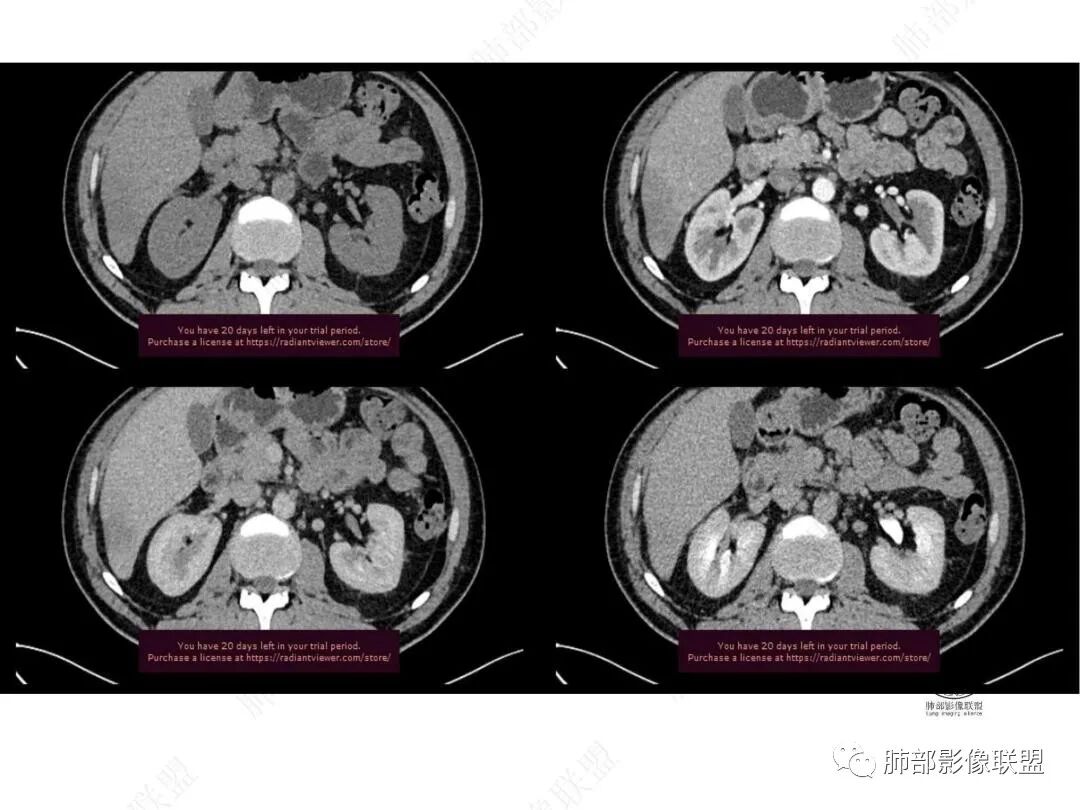

平扫图像

增强图像

CT值信息

中年男性,反复低热3月伴近期乏力及右上腹隐痛,白细胞,中性粒及淀粉样蛋白A增高,PCT不高,IGA、IGg增高,类风湿因子增高,未提供IGg4水平,影像改变,左侧肋骨陈旧性骨折(2020年已存在)右上叶前段胸骨旁的胸膜下新发病灶,支气管进入后一段才堵塞,肺动脉进入,走行自然,未见破坏,明显均匀强化,气管及支气管壁有增厚,钙化,纵隔内淋巴结增大,均匀强化,无坏死,纵隔内脂肪混浊,局部强化,肝内低密度灶,延迟强化(肺内病灶,淋巴结、混浊脂肪,肝内病灶强化均一致,且均为延迟强化)。初步考虑:免疫相关性炎症,IGg4相关炎症可能大,依据:IGA、IGg增高(未提供IGg4,可能是故意隐藏了),类风湿因子增高,炎性指标增高,但PCT不高,细菌感染可能就变小,加上病变同时累及肺、纵隔淋巴结,纵隔内脂肪、肝。

肝脏病变明确,是轻度强化,延迟强化特点,边缘模糊,有轻微的包膜挛缩。

4.肝脏病灶没有假包膜,没有动脉早期强化,没有肝硬化,未见扩张胆管,未见环形强化,也未显示靶征,缺乏肝细胞肝癌、胆管细胞癌、转移癌或肝脓肿特征。

但回顾性分析,如此少血供确实可以符合淋巴瘤,如果密度更均匀一点的话,这是我们有所忽略的地方。

5.淋巴瘤可以解释影像改变,但仅凭影像及临床很难想到它是霍奇金!结外病变主攻方向以肝组织、肺组织为主,还突破胸膜?